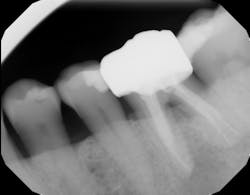

Technology solution: Commercially available bone grafts, such as Geistlich Bio-Oss Collagen, can have components that make them space maintaining as well as act as polymers to absorb and release growth factors and proteins (figure 5). By adding growth-stimulating factors/proteins to your regular bone grafts (figure 6), an increase in osteopromotive potential occurs that can have the ability to overcome a deficiency of bone walls.9 In other words, your bone graft can become alive, and furcations that once were unable to be repaired (figure 7) now have a more predictable success rate10 (figure 8).